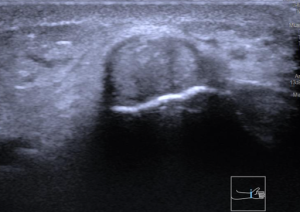

La valoración física y el examen clínico por un médico como la Dra. Vivian Tecú, es de suma importancia y nos provee el diagnóstico, con tests como el de FINKELSTEIN la probabilidad del diagnóstico aumenta. Sin embargo en la actualidad apoyarse de un estudio diagnóstico como la ecografía de muñeca (ultrasonido de imagen) brinda datos y cambios que confirman el diagnóstico como en las imágenes que vemos abajo.